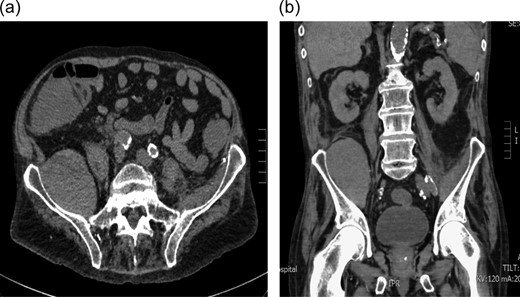

During this admission, balloon aortic valvuloplasty was attempted with right femoral artery access obtained via a right groin puncture; unfortunately, the patient became hemodynamically unstable and the procedure was abandoned. Two weeks later, the patient started complaining of severe pain in the right hip. Examination revealed extensive bruising overlying the right groin and decreased hip flexion on the right side with diminished power in the L3–S1 myotomes. Additionally, there was patchy loss of sensation to the anterior right thigh and the dorsum of the right foot. A Doppler ultrasound of the right groin was performed which revealed a 2 cm false aneurysm in the right groin medial to the right common femoral artery. A non-contrast computed tomography (CT) scan was also performed which revealed areas of mesenteric stranding in the right iliac fossa with an enlarged right iliacus muscle measuring 7 × 6.5 cm. The iliacus muscle demonstrated subtle low-attenuation areas in keeping with an iliacus hematoma (Fig. 1a and b).

(a and b) Axial and coronal computerized tomography scans demonstrating a large iliacus hematoma in the right iliac fossa.